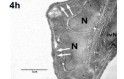

Migration neutrophiler Granulozyten in die verschiedenen Kompartimente der Lunge

Die chemokininduzierte Einwanderung neutrophiler Granulozyten in die Lunge ist ein zentraler pathophysiologischer Mechanismus im Rahmen des akuten Lungenversagens. Die zentrale Bedeutung von DARC für die Konzentration zirkulierender Chemokine impliziert eine mögliche Rolle bei der Entstehung des akuten Lungenversagens.